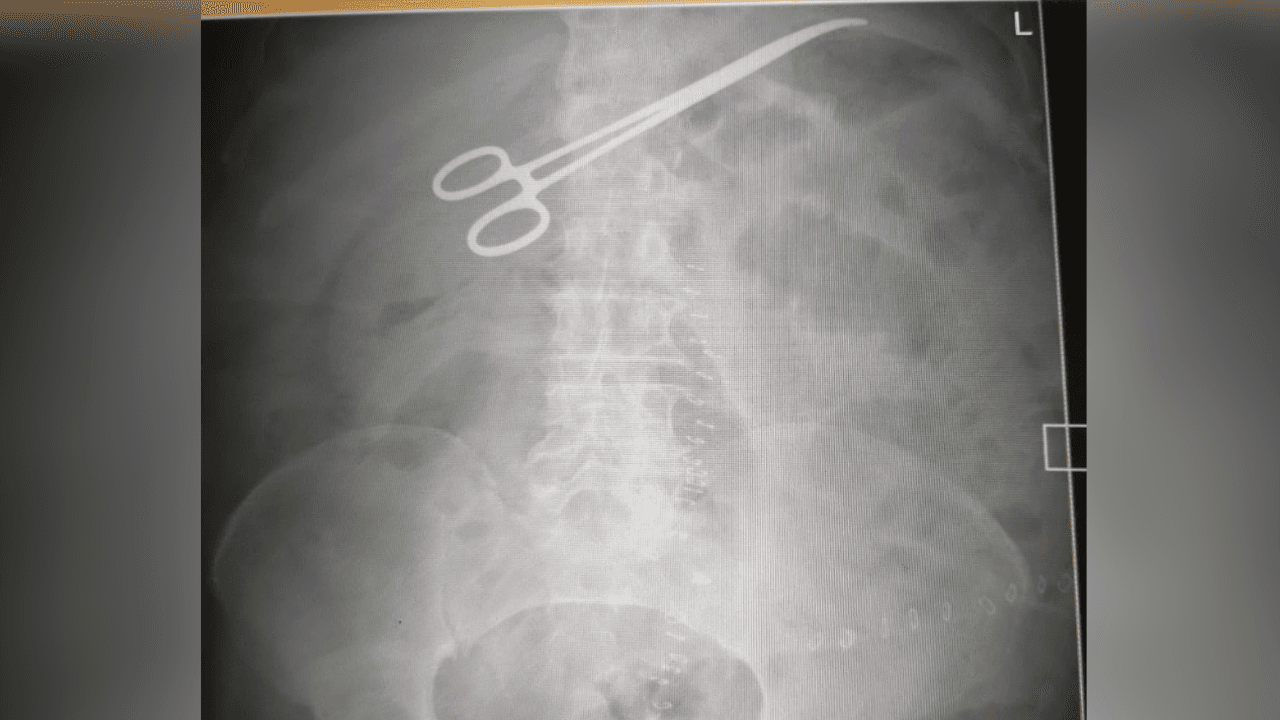

صورة أشعةالأربعاء، 26-11-2025